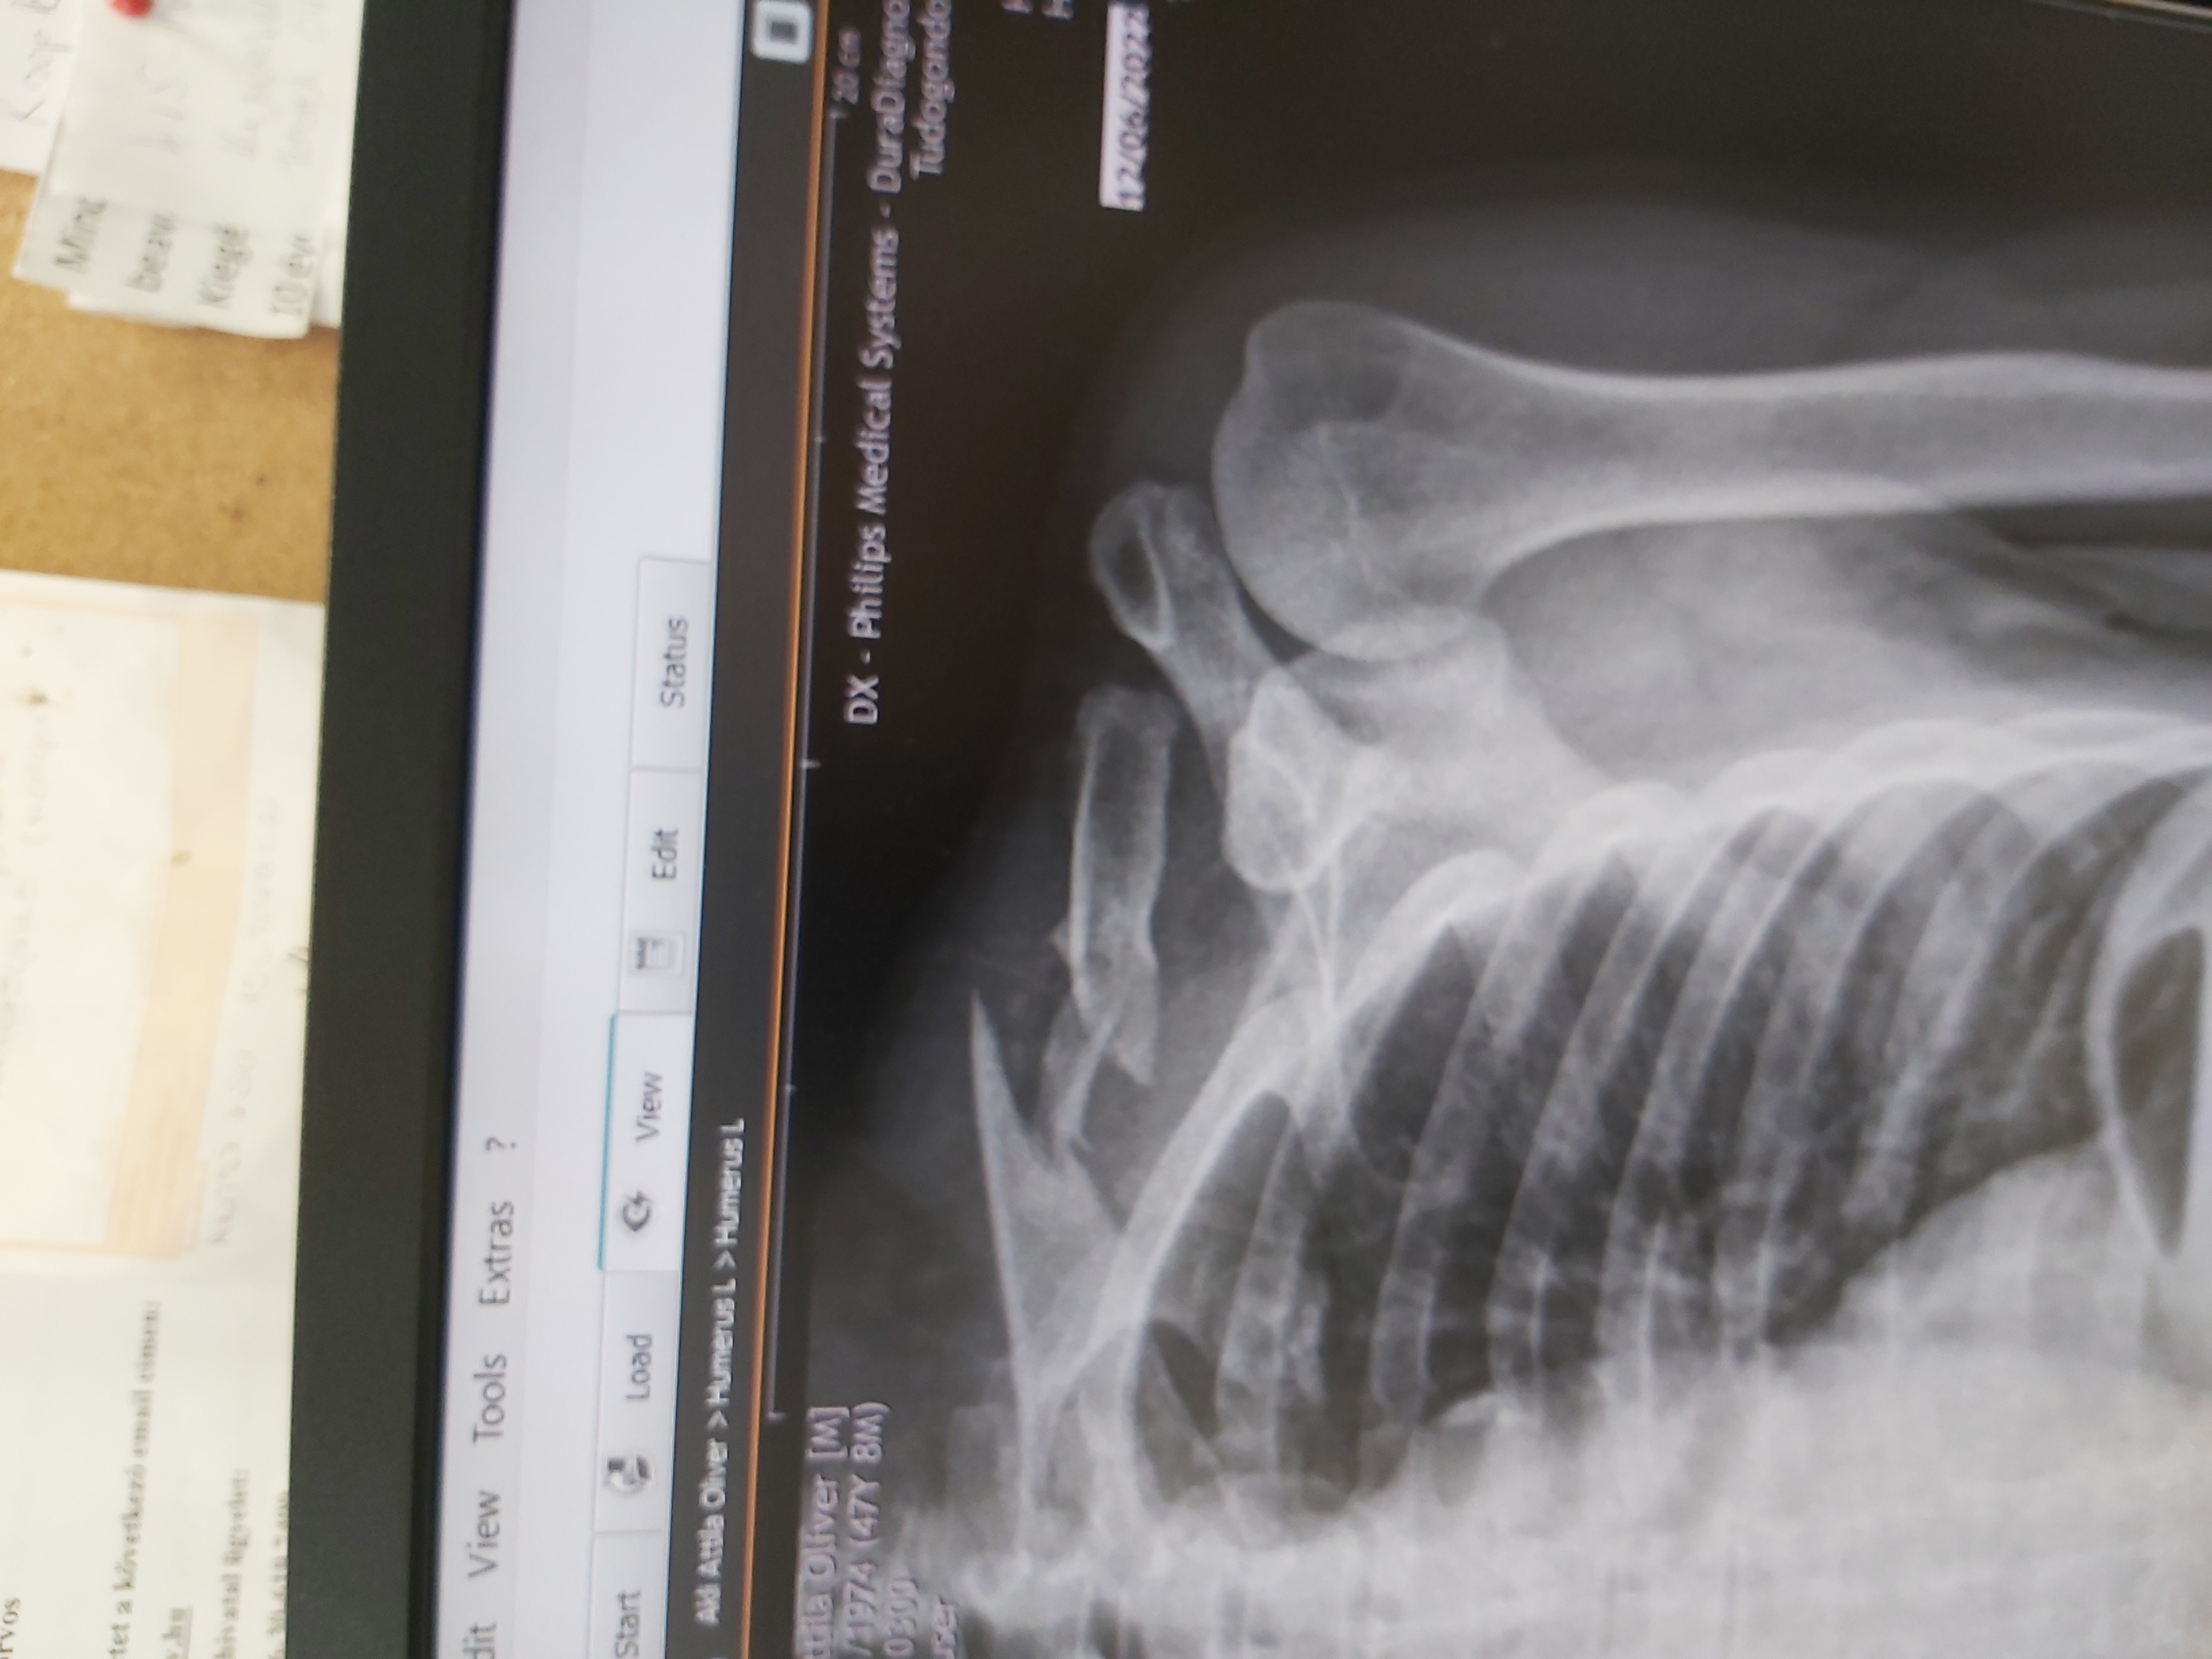

Mutattam páromnak a röntgent; az első reakciója az volt, hogy műtét. Mondjuk ő tényleg nem tegnap végzett, úgyhogy nem követi az új "divatokat".

Ezt a kulcscsontot meg kell tűzni az biztos szinte. Rotátorköpeny nem szakadt el? Csont összeforr, de a rotátor sose lesz jó, ha elszakad. Rengeteg gyógytorna kell majd, az biztos.AAttila írta: ↑2022.06.14., kedd 13:29Holnap megyünk a Merényibe. Meglátjuk mit mondanak,mert tegnapig még kiállt az a darab csont, de éjszaka tornáztattam,mozgattam és visszament. Most sima egyenes. Kell egy újabb röntgen. A sportkórházban azt mondták,hogy TB-re augusztus vége, maszekban ugyanaz az orvos jövő héten megcsinálná 700e forintért. Azt is mondták,hogy ma már " nem divat' műteni, ha a helyén van minden,akkor nem nyúlnak bele feleslegesen, hagyják magától összeforrni. Majd kiderül.

Holnap megyünk a Merényibe. Meglátjuk mit mondanak,mert tegnapig még kiállt az a darab csont, de éjszaka tornáztattam,mozgattam és visszament. Most sima egyenes. Kell egy újabb röntgen. A sportkórházban azt mondták,hogy TB-re augusztus vége, maszekban ugyanaz az orvos jövő héten megcsinálná 700e forintért. Azt is mondták,hogy ma már " nem divat' műteni, ha a helyén van minden,akkor nem nyúlnak bele feleslegesen, hagyják magától összeforrni. Majd kiderül.